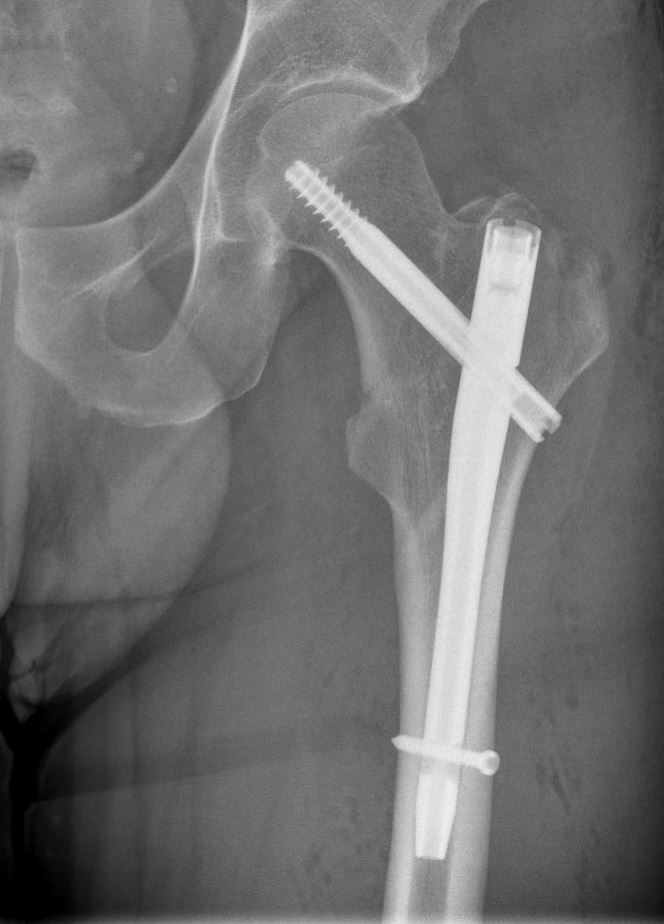

Operatie: in de meerderheid van de gevallen is er een indicatie voor operatie. Het doel van de operatie is de patiënt pijnvrij te krijgen en zo snel mogelijk weer uit bed te krijgen, aangezien patiënten snel zieker worden als ze alleen maar in bed kunnen blijven liggen (ontstaan van oa. longontstekingen en doorligplekken) Het soort operatie is afhankelijk van onder andere de leeftijd van de patiënt, de plaats van de breuk en de stand van de breuk. Als de breuk in de nek van de heup zit (vlak onder de kop), dan zal er gekozen worden voor het vastzetten van de heupkop met bijvoorbeeld 1 of meer stevige schroeven in de heupkop, of voor het vervangen van de heupkop met een heupprothese. Indien de breuk onder de nek en dus meer in het bovenbeen zit, zal er gekozen worden voor of een stevige schroef in een plaat, of voor een stevige schroef met een pen in het bovenbeensbot.